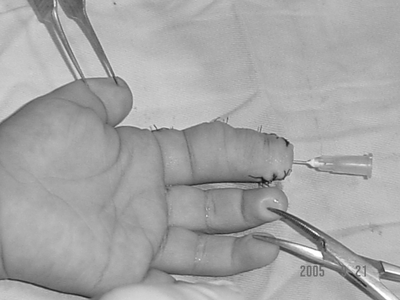

性别:女      年龄:8个月     双手多指畸形

诊断:右手多指切除,拇外展,拇短伸重建术,石膏外固定术